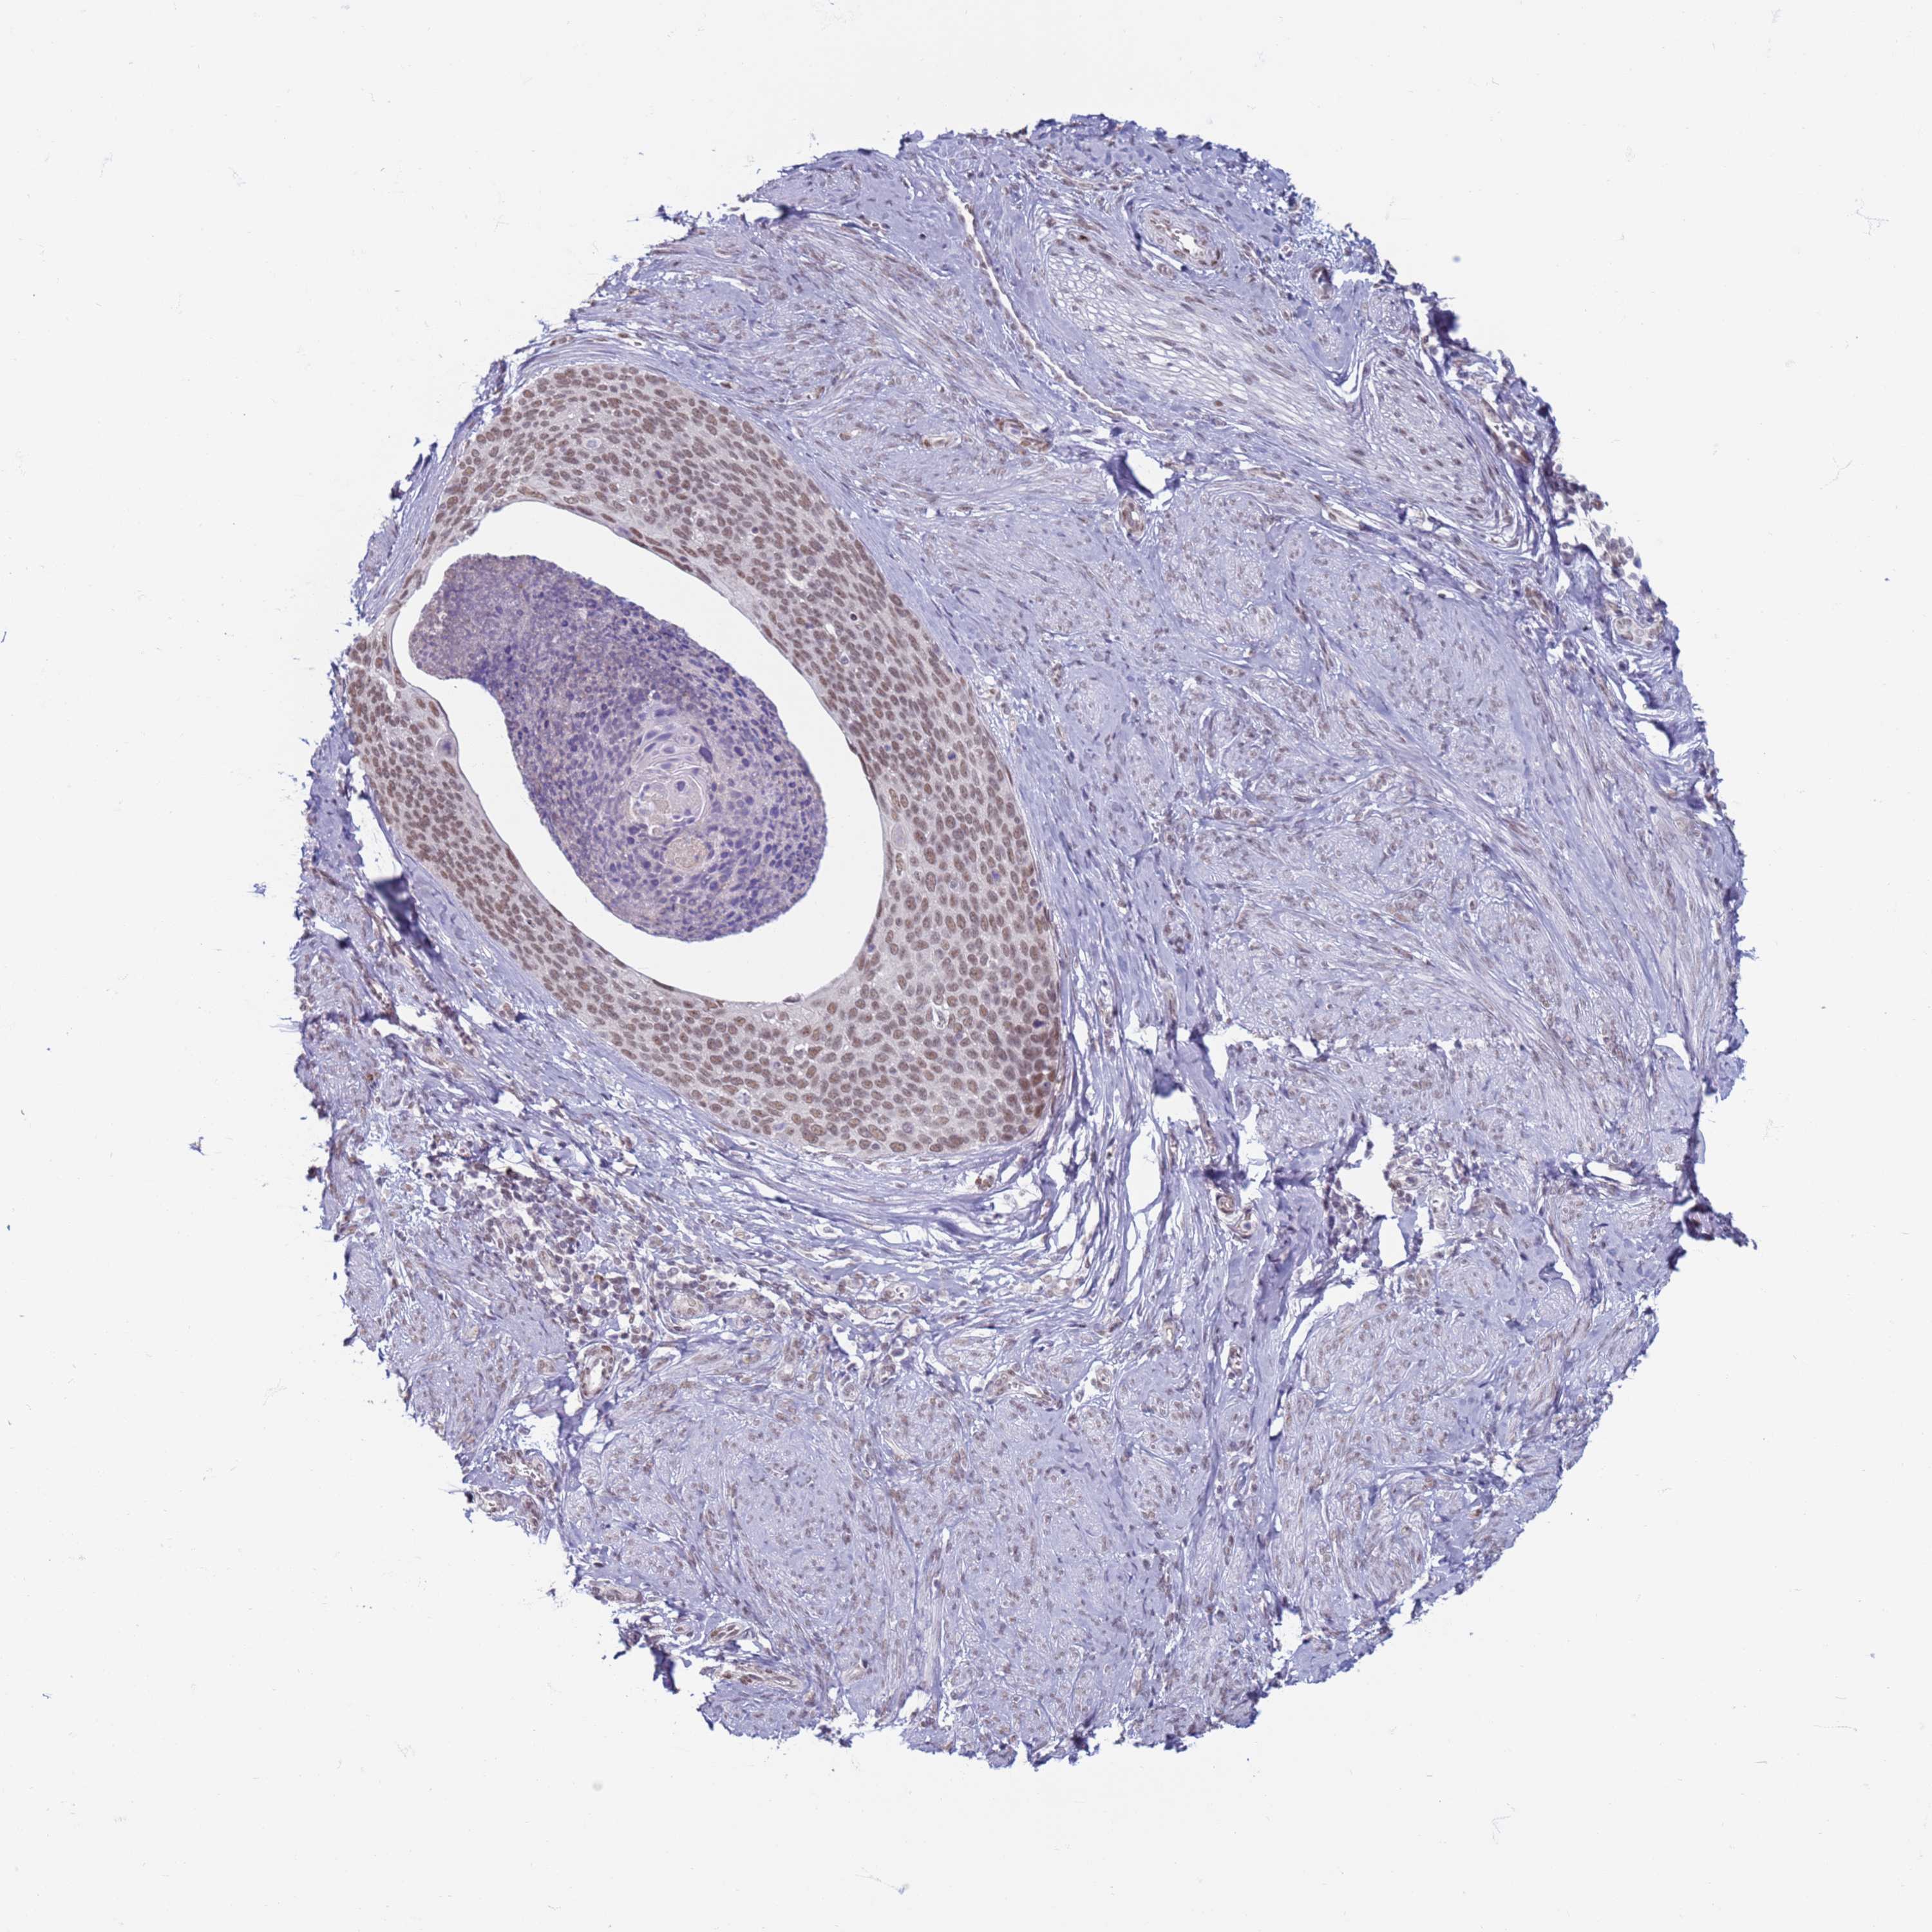

CERVICAL CANCER - Protein expressioni

A mouse-over function shows sample information and annotation data. Click on an image to view it in a full screen mode. Samples can be filtered based on level of antibody staining by selecting one or several of the following categories: high, medium, low and not detected. The assay and annotation is described here.

Note that samples used for immunohistochemistry by the Human Protein Atlas do not correspond to samples in the TCGA dataset.

Antibody stainingi

Antibody staining in the annotated cell types in the current human tissue is reported as not detected, low, medium, or high, based on conventional immunohistochemistry profiling in selected tissues. This score is based on the combination of the staining intensity and fraction of stained cells.

Each image is clickable and will lead to virtual microscopy that enables deeper exploration of all samples and also displays staining intensity scores, fraction scores and subcellular localization as well as patient and tissue information for each sample.

Antibody HPA041906

Antibody HPA043552

Staining

High

Medium

Low

Not detected

Intensity

Strong

Moderate

Weak

Negative

Quantity

>75%

75%-25%

<25%

None

Location

Nuclear

Cytoplasmic/membranous

Cytoplasmic/membranous,nuclear

Squamous cell carcinoma, NOS

Adenocarcinoma, NOS